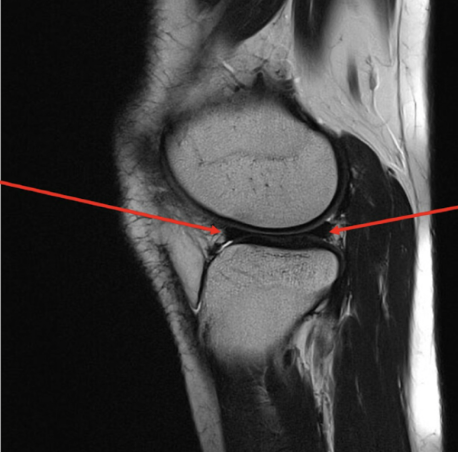

Pathology

• Medial collateral ligament tear

• High signal intensity within the

medial aspect of the knee indicative of fluid presence as a result of a pathological process in this case the tear.